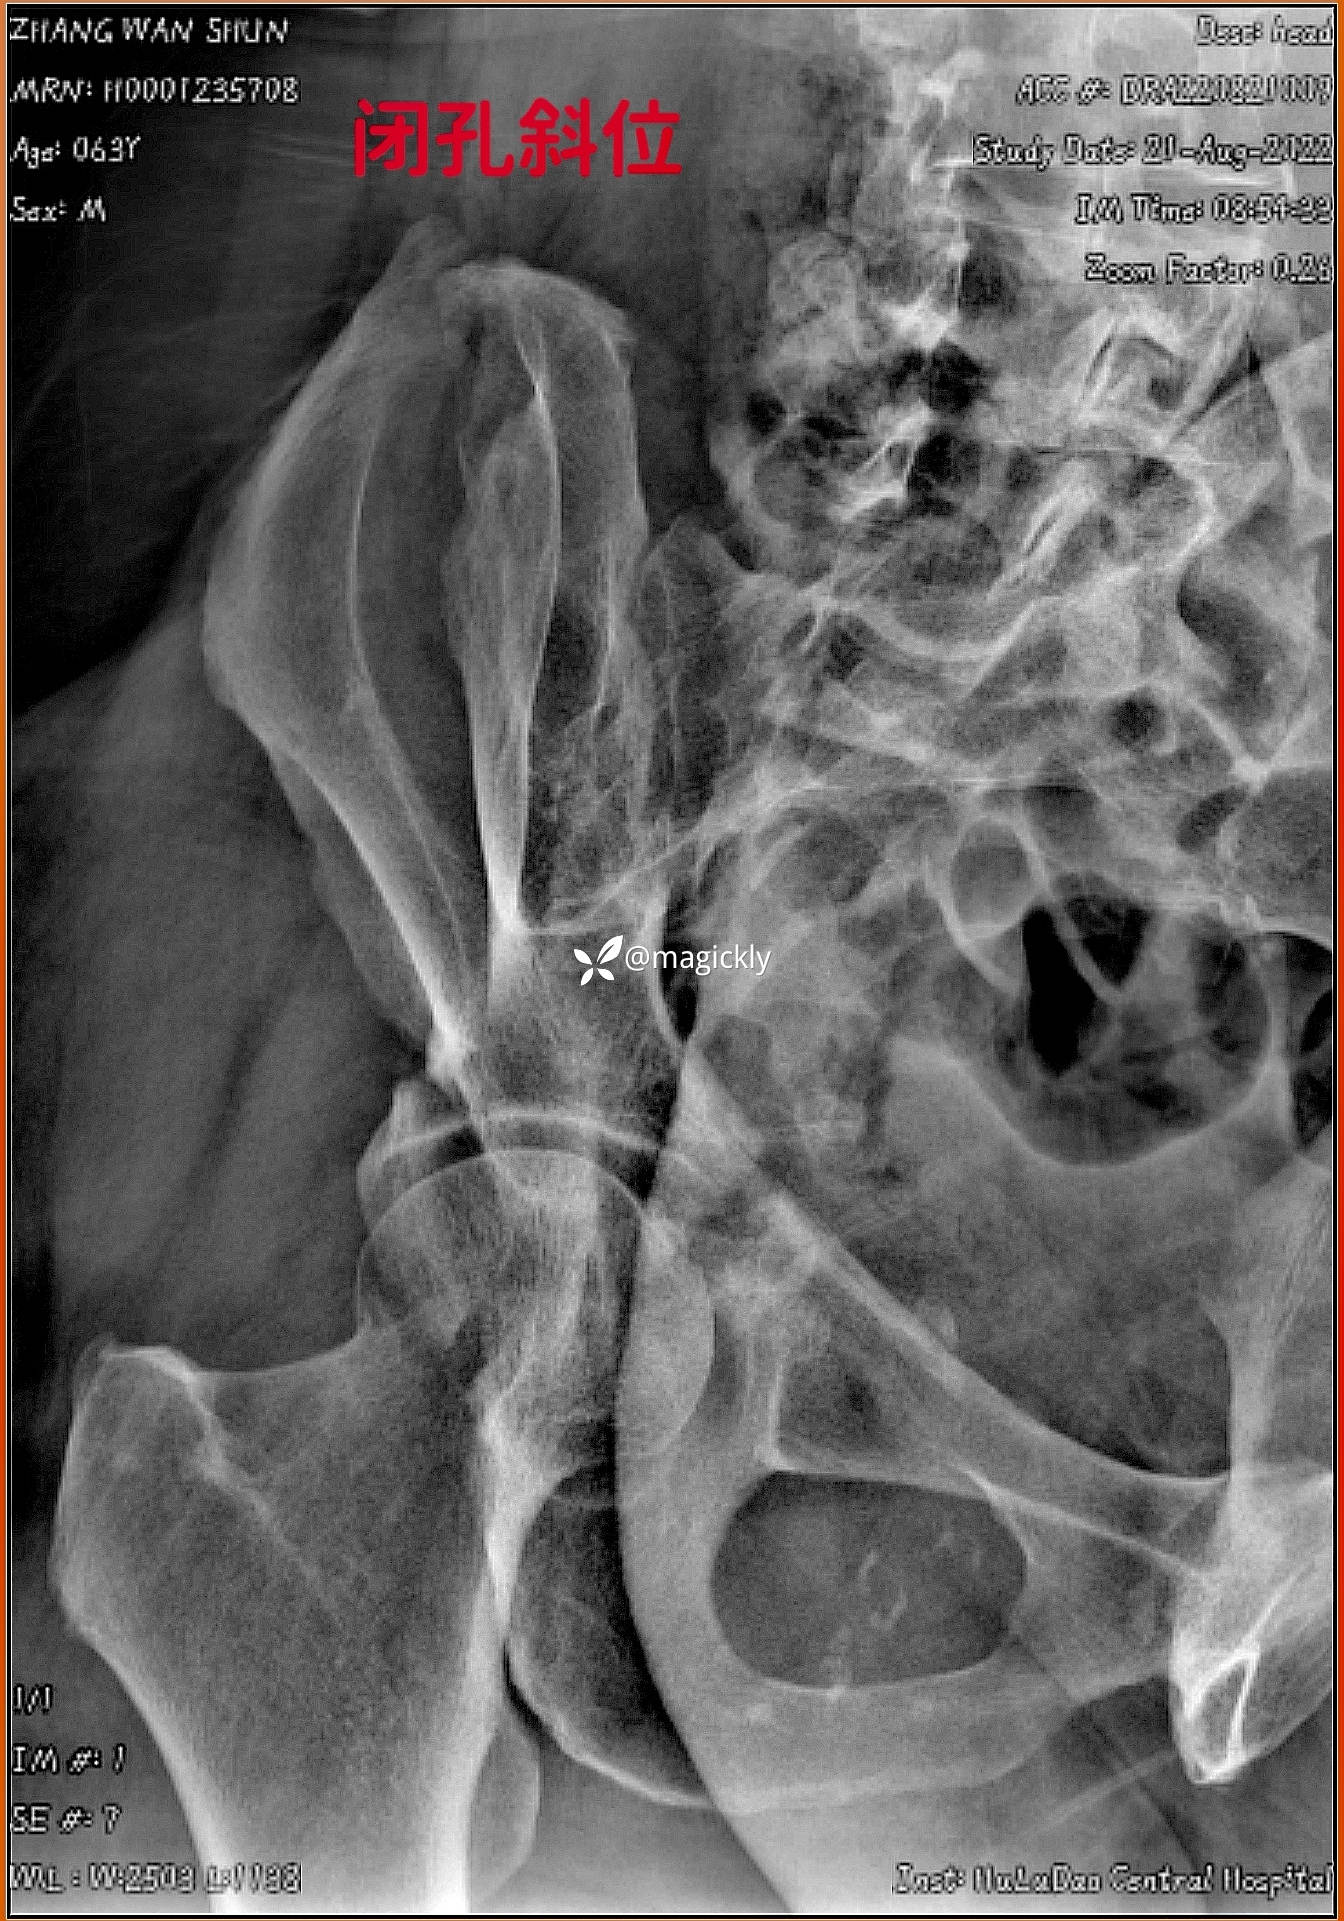

【患者信息】:男患,老年。

【主诉】:重物咋伤后右侧髋部疼痛、活动受限。

【检查】:局部体征明确,影像学结果如下

【临床诊断】:髋臼骨折(后上壁)